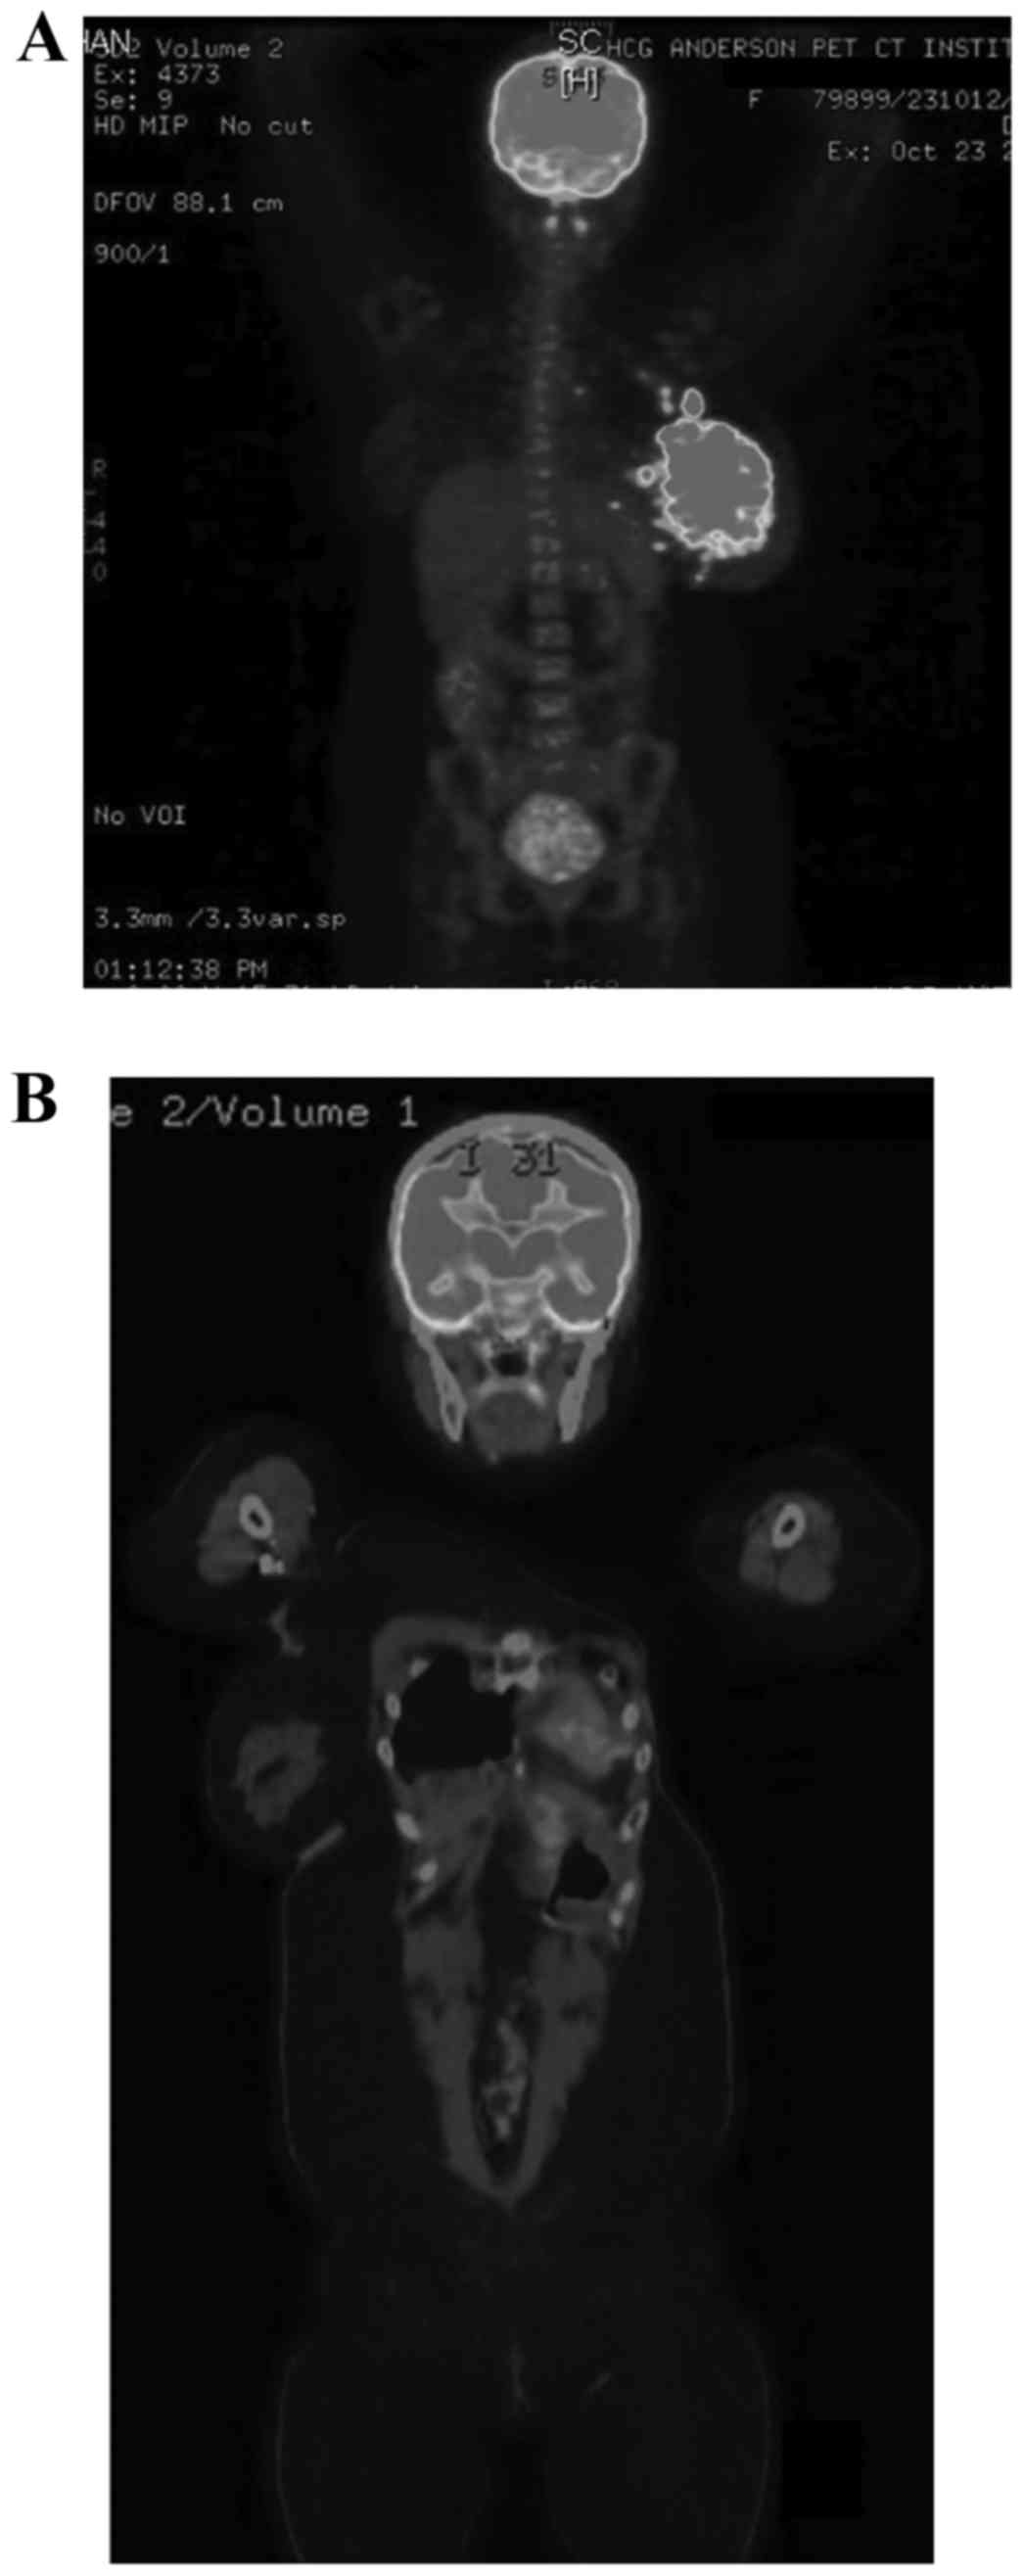

Following preliminary investigations, a Tru-Cut biopsy in October 2012 revealed infiltrating lobular carcinoma of the left breast. The cancer was aggressive and inflammatory in nature, with rapidly progressing breast tenderness, pain and erythema. Whole-body positron emission tomography-computed tomography (PET-CT) scanning revealed a metabolically active large lobulated heterogeneously enhancing lesion (12.4×7.4 cm) (Fig. 1A), involving all quadrants of the left breast with diffuse left breast skin thickening and multiple discrete satellite nodules (<15 mm) surrounding the mass lesion and metabolically active multiple left axillary, pectoral and left upper internal mammary lymph nodes (Fig. 1A). Immunohistochemistry revealed histological characteristics compatible with infiltrating ductal carcinoma of the breast (Bloom & Richardson's provisional Grade 8) (13) ER-positive, PR-negative, Her2/Neu-negative, Ki-67-positive (86%) and EGFR- and cytokeratin 5-negative. The patient underwent three cycles of preoperative chemotherapy (between October 2012 and December 2012) with doxorubicin, docetaxel and cyclophosphamide, followed by left modified radical mastectomy (December 2012) followed by three cycles of postoperative chemotherapy (between January and February 2013). The histopathological examination following the surgery and chemotherapy established the tumor to be pT3 N2a Mx stage IIIA (14).

Figure 1.

Whole-body positron emission tomography-computed tomography. (A) Image taken prior to the start of the treatments. (B) Follow-up scan image in March 2015, showing no evidence of mass lesions or enlarged lymph nodes.

Fig. 2A presents the total number of leukocytes, which remained close to normal throughout the therapy. Fig. 2B shows the declining NK cell counts following their in vitro expansion, parallel to subsequent chemotherapy cycles, and the decrease became more profound after the surgery. There were no adverse reactions following the AIET. Despite the decreased NK cells counts after in vitro expansion, there was a subjective improvement in the quality of life after AIET and the patient reported improved tolerance to the side effects of the chemotherapy, possibly as AIET was administered concurrently. The patient has been disease-free for >28 months and a PET-CT scan in February 2014 identified no evidence of recurrence. Follow-up scans in June 2014 and March 2015 (Fig. 1B) also reported that there was no evidence of any mass lesion or large lymph nodes in the abdomen or the pelvis. Fig. 3 depicts the timeline of the interventions and outcomes.